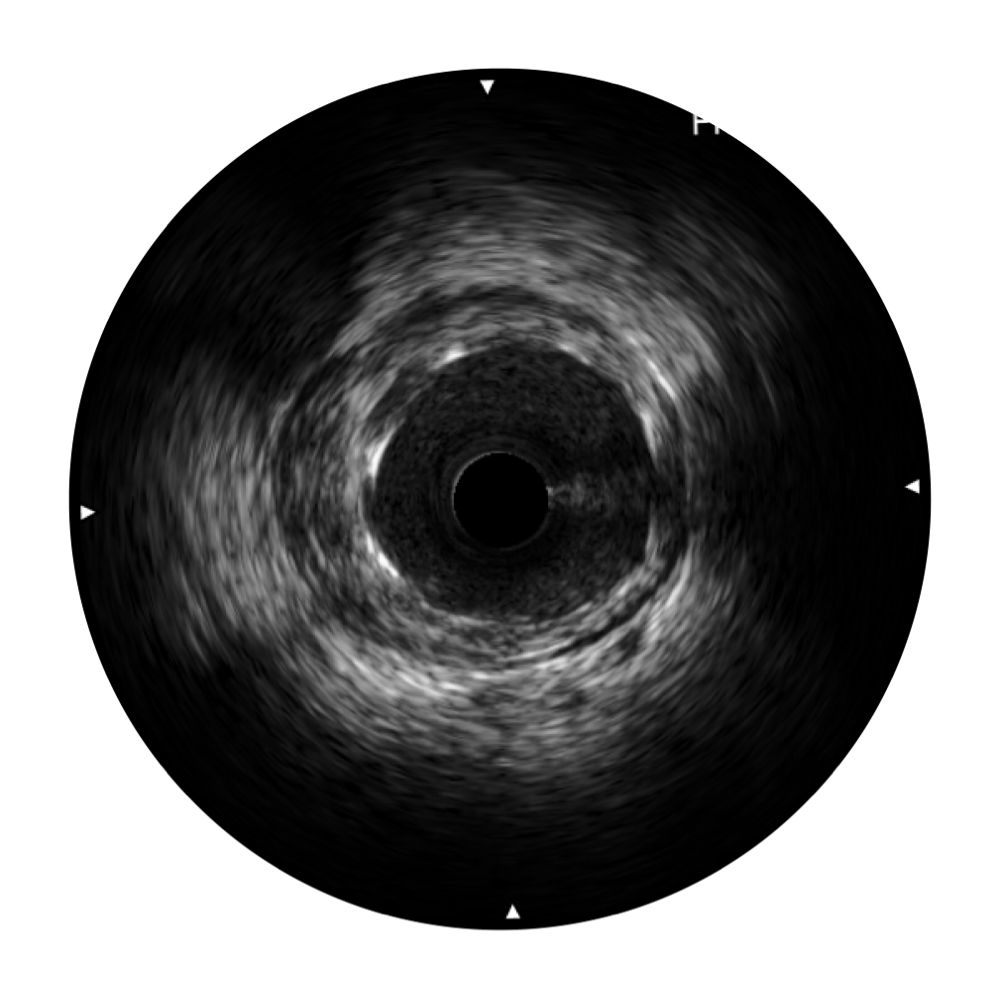

传统IVUS图像

对比传统IVUS导管成像,环球UG官网宽频IVUS图像的近场支架梁显影更细腻,远场中膜外血管仍清晰可辨,兼顾远中近,兼顾分辨力与穿透深度